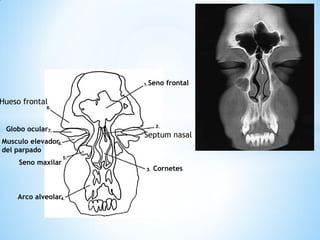

Seno frontal

Globo ocular

Musculo elevador del parpado

Seno maxilar

Arco alveolar

Cornetes

Hueso frontal

Septum nasal

Seno frontal Globoocular Musculo elevador del parpado Seno maxilar Arco alveolar Cornetes Hueso frontal Septum nasal

Seno frontal Globoocular Musculo elevador Del parpado Seno maxilar Arco alveolar Septum nasal Hueso frontal cornetes